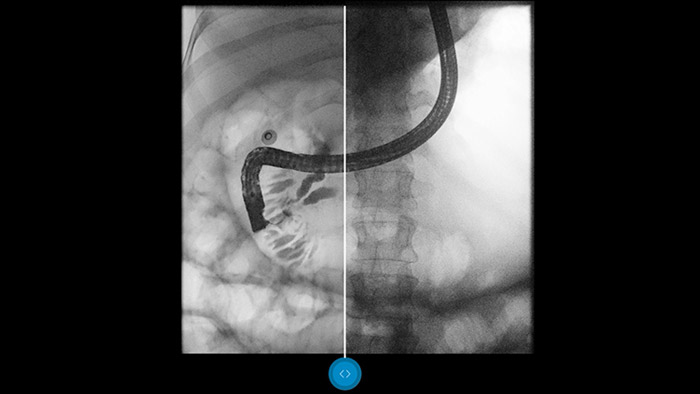

Compárelo con un procesador de imágenes convencional para ver los beneficios usted mismo.

Dynamic UNIQUE ofrece una excelente visibilidad de los detalles con supresión del ruido en tiempo real, desde el primer fotograma hasta el último. La información de diagnóstico para cada fotograma se muestra con gran claridad, con el brillo correcto y con una latencia muy baja. La representación de la imagen es coherente y estable, incluso cuando el contenido de la imagen varía rápidamente. Dynamic UNIQUE admite exámenes rápidos y seguros con dosis bajas al proporcionar claridad de detalle para mejorar su confianza en el diagnóstico.

El software de procesamiento de imágenes Dynamic UNIQUE equilibra el contraste. Además, realza los detalles más débiles y brinda una calidad de imagen uniforme, lo cual permite distinguir claramente los huesos de los tejidos blandos.